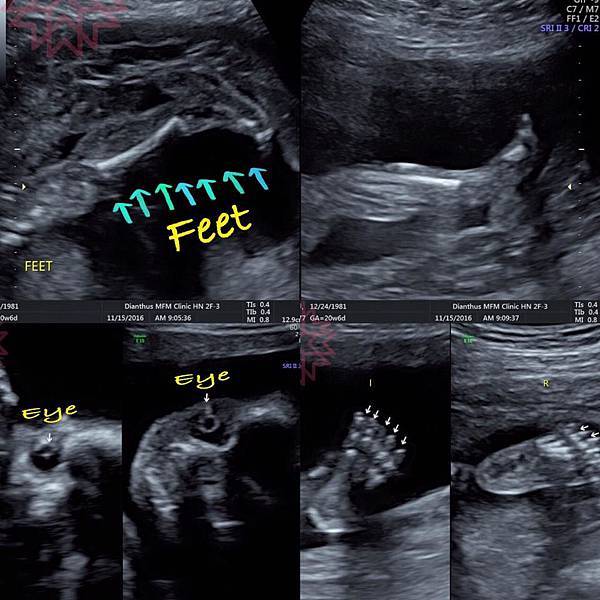

終於來到21W的高層次超音波,這是檢查胎兒器官發育的重要檢查

而且姿勢很配合,順利地從頭、眼、鼻、唇、四肢、手指腳趾、心肝脾肺腎胃膽都看得一清二楚

判別超音波真的好難啊,我們外行人怎麼看都是黑白雜訊

技術師和醫生竟然可以從這小黑洞看出是肺還是腎臟實在是太厲害了

高層次超音波對於新生兒缺損只有80%的檢出率

實際檢查過就知道這已經是難能可貴的數字,醫療人員不知道要累積多久的經驗才能正確判讀

這張有蛋包的眼睛,雖然我是她媽還是要說:你不要這樣看我我好害怕XDDD

腿一直在踢我的肚子!一直踢!!!